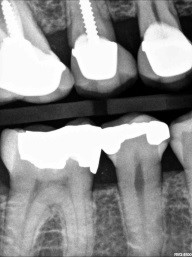

Patient 1: Tooth #12

This patient, who presented in 2015, brought her 2013 black-and-white image with her (the first images above). The second set of black and white images are from 2015. Notice the change in the interproximal caries. Even with a significant change (hypothetical) in a patient’s habit and fluoride delivery, how do these types of caries arrest predictably?